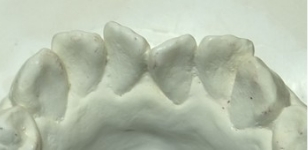

2):当院の矯正の調査法(世界的権威リトル教授の調査方法)

観察方法はPARスコアではなく、もう少しダイレクトな評価になるリトル教授らの方法を使いました。つまり右図のように、後戻りが一番現れやすいと言われている下の前歯において、歯と歯の接触点間の距離をmm単位でデジタル写真上で計測し、それらの合計のミリ数を「指数」とするものです。歯並びが綺麗であれば“0”に近い数字になり、数字が大きいと悪い歯並びを意味します。この写真の歯と歯の接触点間の距離の合計は9.3mmでしたから、指数は9.3になります。